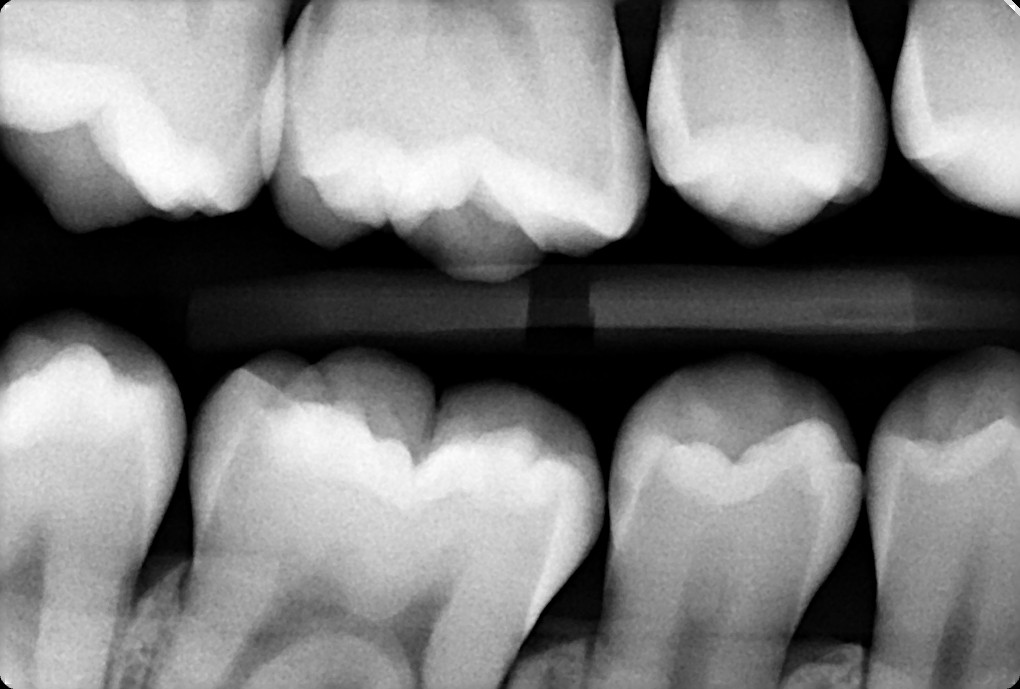

1.  In the X ray bellow for which jaw periodontal bone loss is evident?